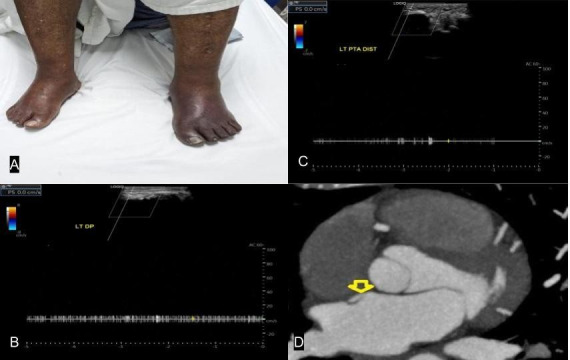

Acute limb ischemia, or ALI, is a rapid decrease in limb perfusion due to an occlusion of an artery or a bypass graft. Most cases result from in situ thrombosis or embolism in patients with antecedent peripheral arterial disease. Potential sources of arterial embolism as a cause of this condition include cardiogenic, aortic, peripheral aneurysms with an associated mural thrombus or, less commonly, a paradoxical embolism through a septal defect. We present a rare case of ALI due to an underlying patent foramen ovale that was successfully treated following revascularization. This article emphasizes one of the more unusual mechanisms of ALI. Despite the rarity, physicians should maintain a high index of clinical suspicion for a paradoxical embolism across a patent foramen ovale in unexplained arterial occlusion. Correct mechanism identification ensures adequate referral and prompt treatment that may reduce complications.